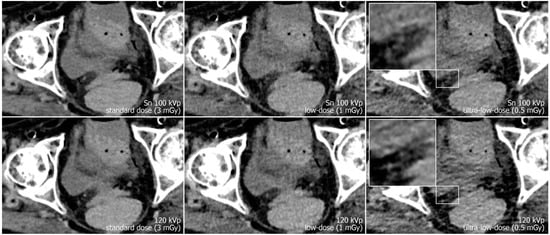

Reconstruction of datasets followed identical parameters: slice thickness and increment were set to 3 mm each, and the field of view to 400 mm with a 512 × 512 pixel matrix. A soft tissue convolution kernel (Br36) was applied with the highest strength level of a dedicated quantum iterative reconstruction algorithm (QIR 4). For polychromatic scans, “T3D” mode was enabled, which includes photon energies between 20 and 120 keV [29]. Window settings were pre-set to 300/40 Hounsfield units (width/center) were employed for dedicated analysis of soft tissue. However, readers were given the possibility to adjust these settings at will during image quality assessment. Examples regarding differences in image quality of the pelvic region between acquisition protocols are provided in Figure 1, while Figure 2 illustrates the encumbered demarcability of the lower Ureter in ultra-low-dose scans.

Figure 1.

Axial view of the left distal ureter (arrow). Note the impaired image quality due to hypodense streak artifacts in polychromatic scans at 120 kVp (lower row), especially with ultra-low radiation dose. (The arrow marks the left ureter with an adjacent phlebolite.)